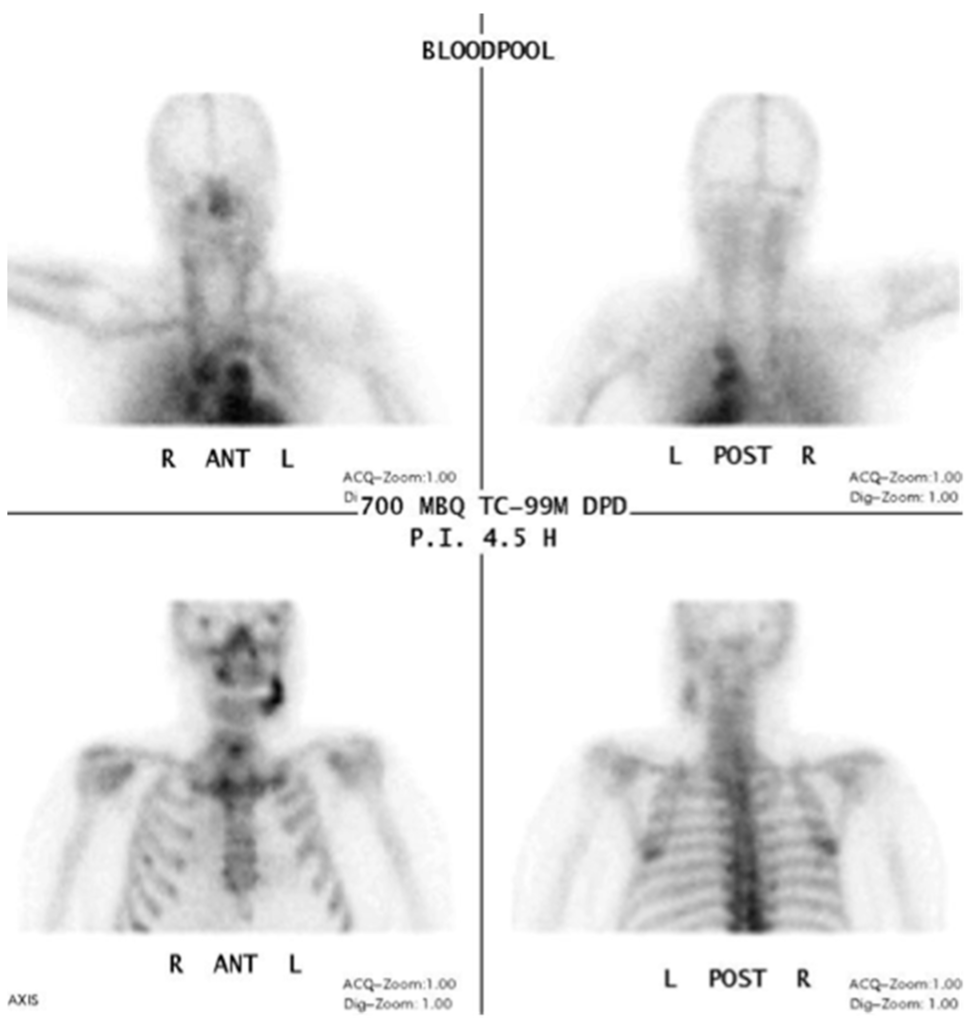

Information from a planar scintigraphy is displayed in a two-dimensional form in contrast to SPECT. An example of technetium-99m-3,3-diphosphono-1,2-propanodicarboxylicacid (99Tcm-DPD) SPECT and 99Tcm-DPD SPECT/CT is seen in Figure 8 and Figure 9 respectively.

Figure 8.

Planar scintigraphy (Siemens, Symbia) Blood pool phase. Patient: 66 years old, male, secondary osteoporosis due to castration, alendronate. AAMOS staging: stage 3.

In SPECT imaging, the distribution of the radionuclide is monitored in multiple two-dimensional images and from multiple angles. From these datasets, a three-dimensional image is then calculated. If anatomical imaging should be added, hybrid SPECT/CT scanners are available. For detecting bony infections, technetium-99m methylene diphosphonate (99Tcm-MDP) or technetium-99 m-DPD (99Tcm-DPD) are frequently used nuclides; they show no significant differences in detecting “pathologically increased bone uptake” [47]. MRONJ should not show an uptake in the necrotic zone, but due to the associated infection, a nuclide uptake may be seen. O’Ryan et al. [48] published a retrospective study on MRONJ patients who had received whole-body planar bone scintigraphy. They used the following scoring system for the jaw: “score 0, no visual evidence of increased uptake was present; score 1, uptake was mild and equal to that in the sternum; and score 2, uptake was intense and greater than that in the sternum” [48]. The comparison with the sternum uptake was based on a paper published by Kakhki et al. [49]. Kakhki et al.’s paper, a study on 334 patients who had no diseases of the sternum/chest wall or malignancy, assessed the normal uptake in a sternum considering the age of the patient [49]. O’Ryan et al. found a nuclide uptake in 65.7% of their MRONJ patients. From their point of view, scintigraphy might have a prognostic value and physicians should watch out for newly occurring uptake in the jaws [48]. Thomas et al. assessed the impact of bone scintigraphy in patients with metastatic castration-resistant prostate cancer who had received bisphosphonates. Their focus was on early prediction of clinically asymptomatic MRONJ. MRONJ was significantly more often developed in patients with a pathological tracer uptake [50]. Ristow et al. investigated the bone turnover in the jaw of breast cancer patients who had received no antiresorptive medication, bisphosphonates, or denosumab. Interestingly, they found that “there was similar turnover of bone in the mandible compared with other skeletal sites (such as the femur), while the maxilla showed significantly higher turnover”. Since the majority of MRONJ lesions occur in the mandible, the bone turnover role of the MRONJ pathogenesis must be further reviewed [51].